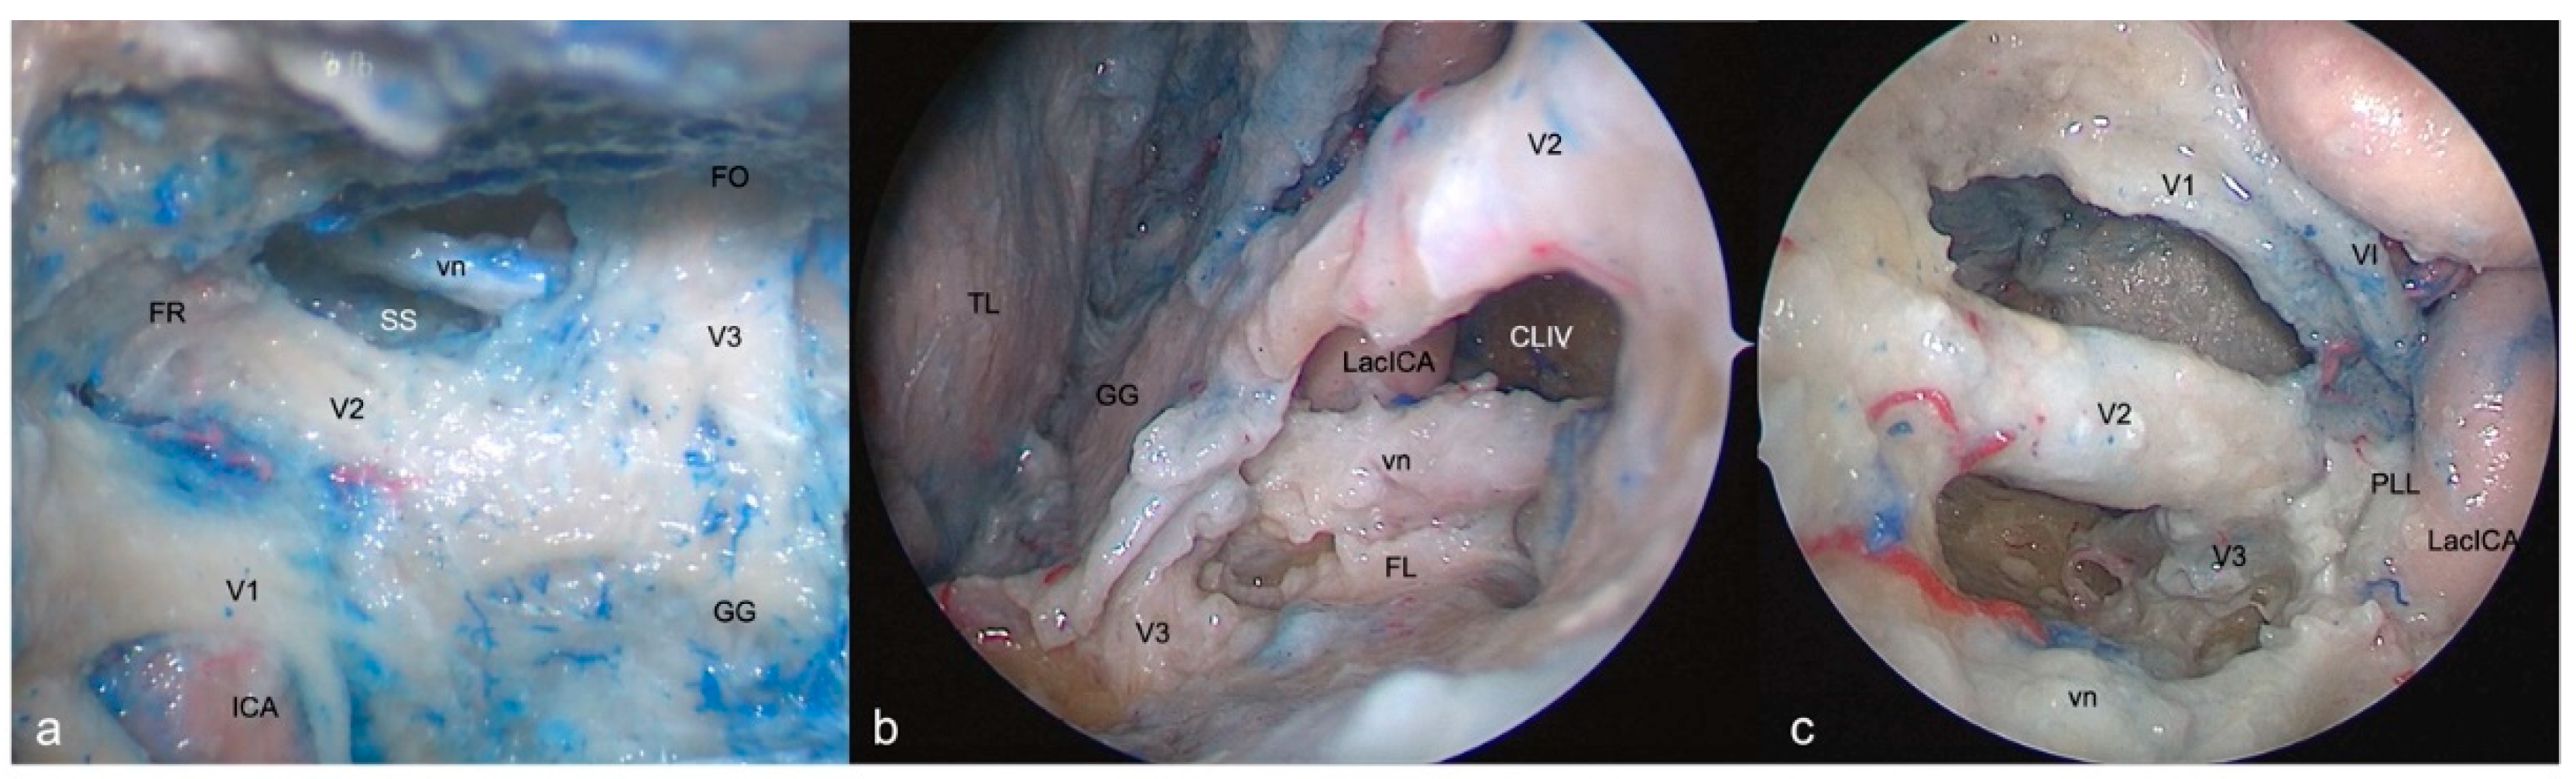

3.5. Anteromedial Triangle (Mullan’s triangle)

3.5.1. FTOZ perspective

This region is delimited superiorly by the lower margin of V1, inferiorly by the upper margin of V2 and anteriorly by the line connecting the point where the ophthalmic nerve enters superior orbital fissure and the point where the maxillary nerve enters foramen rotundum (Figure 4a). The removal of the outer bony shell of this triangle leads into the sphenoid sinus.

3.5.2. SETOA perspective

This region comes immediately into the endoscopic view after interperiosteal-dura dissection of the lateral wall of CS and is the largest safe entry zone to the CS. Unlike the transcranial fronto-temporal point of view, where no segments of ICA are visible in this area, the SETOA allows to disclose in the depth, at the apex of this triangle, where V1 and V2 converge, the inferior half of the posterior ascending segment of the cavernous ICA (C4 segment [24]) after exiting the foramen lacerum, surrounded by sympathetic fibers of the carotid plexus, passing medially to the petro-lingual ligament, to reach the cavernous sinus (Figure 4b). In this triangle, the VI cranial nerve courses almost horizontally, medially to V1 and laterally to the ICA, towards the SOF, and can be visualized after gentle upward retraction of V1 (Figure 4c). One fundamental landmark to guide surgical dissection of the anteromedial triangle, avoiding entering the CS space is the foramen rotundum, which is encountered after resection of the sagittal crest, that discloses V2 inferiorly and outside the CS. Surgical dissection must be performed between the two trigeminal branches at the level of the superior edge of V2, dissecting the perineurium covering the two nerves in an antero-posterior direction, to free the two branches and mobilizing the ophthalmic nerve superiorly, expanding the space between them to get access to the postero-inferior portion of the CS.

3.5.3. EEEA perspective

This area and its content, represented by venous structures, are completely exposed after bone removal of the lateral wall of the sphenoid sinus, with V1 partially hidden by the sixth cranial nerve. The apex of this triangle, where V1 and V2 converge, can be disclosed after medial displacement of the lacerum (C3 segment [24]) and posterior ascending tract of the cavernous (C4 segment [24]) segments of ICA (Figure 4d).

3.6. Anterolateral Triangle

3.6.1. FTOZ perspective

This area is bounded by the lower border of V2, superiorly, the upper border of V3, inferiorly and by the line which connects the foramina rotundum and ovale. The drilling of its medial wall exposes the sphenoid sinus (Figure 5a).

3.6.2. SETOA perspective

The opening of this triangle allows to disclose the vidian nerve and artery in the homonymous canal along their course up to the anterolateral edge of the foramen lacerum, where the posterior opening of the canal is filled with cartilaginous tissue that blends into the more medially positioned cartilage filling the foramen lacerum. The lacerum segment of ICA, at its transition zone from the horizontal petrous to the ascending cavernous segment, medially to the petrolingual ligament, and the related carotid sympathetic plexus, can be exposed also (Figure 5b). As already recently described by our group [36], it is possible to appreciate a space limited by the inferior border of V2, superiorly, the superior border of V3, posteriorly, the line crossing the most anterior limit of exposure of the vidian nerve and joining the foramen rotundum and the point where the greater wing joints the body of the sphenoid bone, anteriorly, and the line between this last point and the foramen ovale posteriorly. This area includes two windows divided by the course of the vidian nerve until where it blends into the cartilaginous tissue of the FL under the trigeminal nerve, and which unfolds different corridors:

a wider superior window (“supravidian”), which discloses two corridors in relationship to the lacerum segments of the ICA: a “medial supravidian corridor” leading to the lower clivus, and a “lateral supravidian corridor” leading, after gentle lateralization of the gasserian ganglion, to the medial aspect of the Meckel’s cave and the terminal portion of the horizontal petrous ICA (pICA).

a narrow inferior window (“infravidian”): which includes the inferior portion of the foramen lacerum distally, and the sphenoid sinus proximally.

3.6.3. EEEA perspective

Whereas V2 is disclosed from the origin up to the foramen rotundum, V3 is recognizable only in its course from the origin at the Gasserian ganglion up to the entrance the foramen ovale (Figure 5c).

Figure 4. Right-side anteromedial (Mullan’s) triangle: FTOZ (a), SETOA (b-c) and EEEA (d) perspectives. This region is delimited superiorly by the lower margin of V1, inferiorly by the upper margin of V2 and anteriorly by the line connecting the point where the ophthalmic nerve enters superior orbital fissure and the point where the maxillary nerve enters foramen rotundum

Figure 5. Right-side anterolateral triangle: FTOZ (a), SETOA (b), EEEA (c) perspectives. This area is bounded by the lower border of V2, superiorly, the upper border of V3, inferiorly and by the line which connects the foramina rotundum and ovale. (red dotted lines: quadrangular space; FO: Foramen Ovale; FR: Foramen Rotundum; GG: Gasserian Ganglion; CLIV: Clivus; Lac ICA: Lacerum Internal Carotid Artery; vn: vidian nerve; FL: Foramen Lacerum; MC: Meckel’s Cave; cICA: cavernous Internal Carotid Artery; pICA: petrous Internal Carotid Artery).